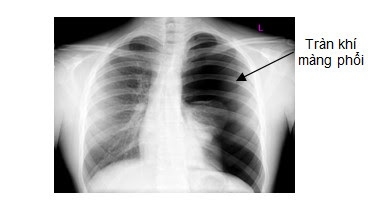

Tràn khí màng phổi do biến chứng viêm phổi

Tràn khí màng phổi thường thứ phát dẫn đến tích tụ khí trong khoang màng phổi do vỡ phế nang hoặc do nhiễm vi trùng sinh hơi.

Khi trẻ bị viêm phổi, gây áp lực trong khoang màng phổi, khiến lồng ngực căng phồng ở bên tổn thương, đẩy lệch trung thất sang bên đối diện, gây tràn khí màng phổi.

Khi thăm khám thấy giảm phế âm bên tràn khí, trẻ thở rên, suy hô hấp nặng và tím tái. Các chẩn đoán phân biệt bao gồm kén phổi, bóng khí phổi, thoát vị hoành.

Cần thực hiện chụp X-quang phổi để đánh giá chi tiết và có biện pháp xử trí sớm.